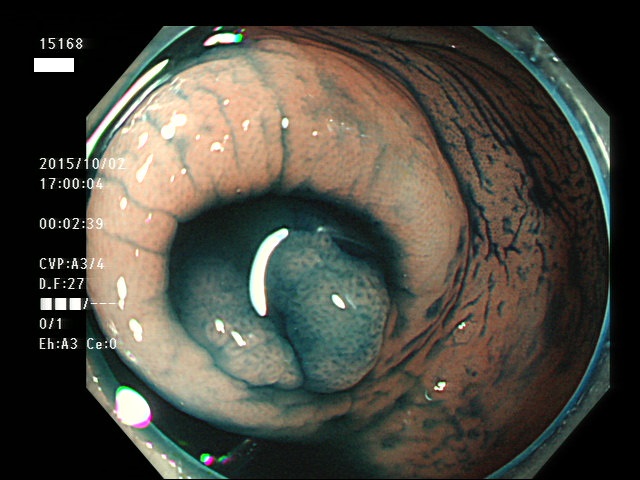

虫垂開口部の過形成ポリープ(SSAP)の例

一般に虫垂過形成ポリープが見られる方は「大腸の他の部位にもポリープ(特にSSAP)が見つかる可能性が非常に高い」のです。つまり「危険な腸である」という警告灯になるのです。虫垂は大腸の一番奥ですから「観察のスタート地点」です。ここで警告灯が出ることは非常に有益な訳です。